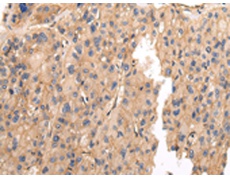

IHC positive control: |

Human prostate cancer and Human thyroid cancer |